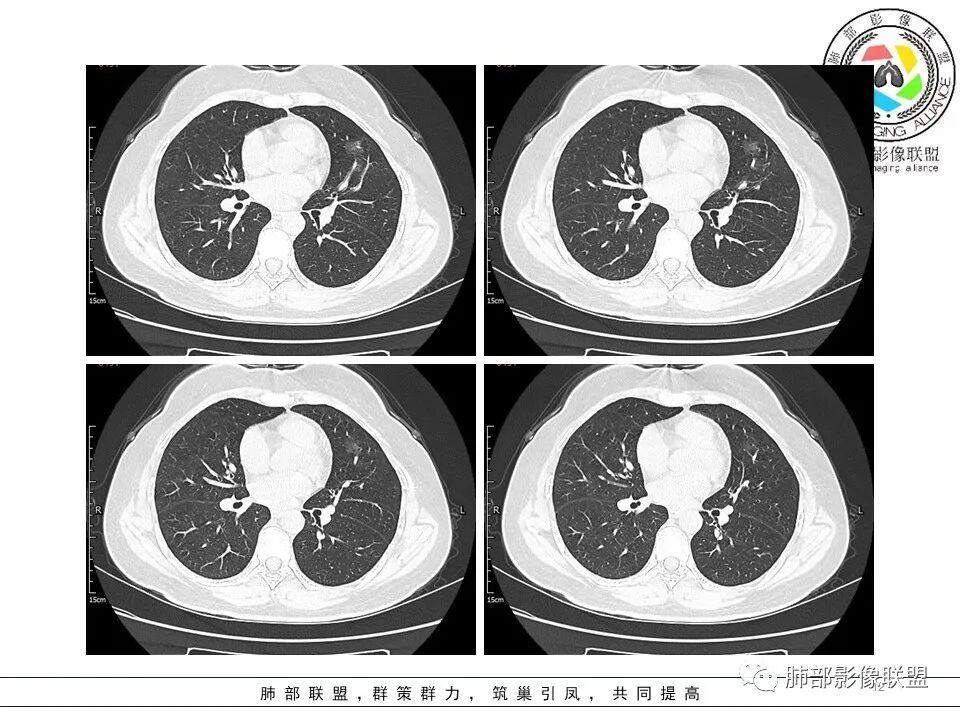

一.大结节影像特点:

左肺上叶胸膜下不规则结节影,分叶、粗短毛刺,胸膜牵拉等,像个“刺头”。

未见钙化,也未显示液化坏死或空洞。

与支气管相关,但取层未能显示支气管进入情况。

有几点应当引起我们高度重视:

1.病灶周围向几个方向膨出的边界清楚的磨玻璃影,这些磨玻璃影时隔几个月依然,几乎可以排除出血及一般的炎性改变。

2.病灶的胸膜牵拉线与其间病灶胸膜侧的磨玻璃边构成朝向胸壁的“月牙铲”结构,这种影像学表现某种程度上反映出病理学特征——病灶收缩+小叶间隔阻挡。

3.病灶实性密度区强化明显,这有助于我们区分一些其他类似病灶,如结核灶等!

4.邻近未见树芽征及卫星灶等。

结合临床,应当高度怀疑浸润性肺腺癌!